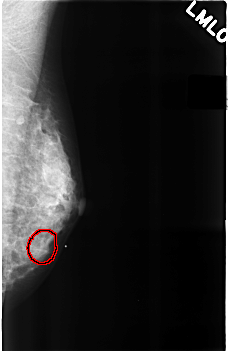

C_0289_1.RIGHT_MLO

LEFT_MLO LINES 4560 PIXELS_PER_LINE 2952 BITS_PER_PIXEL 12 RESOLUTION 50 OVERLAY

FILE: C_0289_1.LEFT_MLO.OVERLAY

TOTAL_ABNORMALITIES 1

ABNORMALITY 1

LESION_TYPE MASS SHAPE ROUND MARGINS OBSCURED

ASSESSMENT 4

SUBTLETY 2

PATHOLOGY BENIGN

TOTAL_OUTLINES 1

BOUNDARY